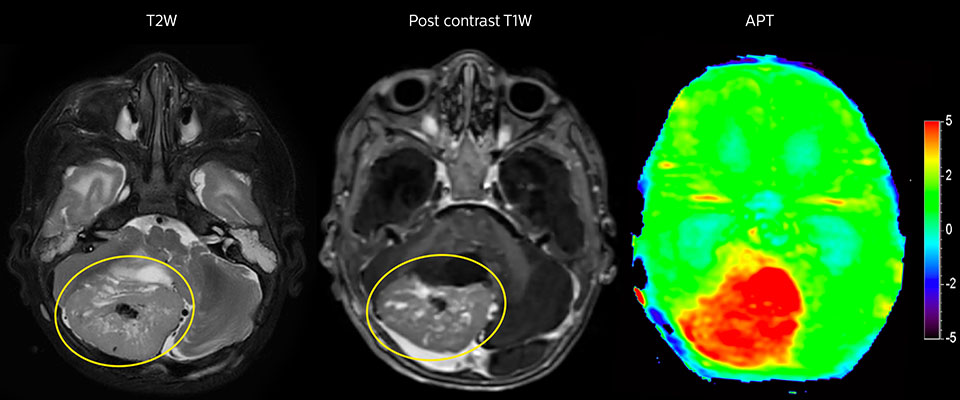

Tumorauswertung bei einem 1-jährigen Kind mit Medulloblastom. Dieser aggressive Tumortyp ist sehr solide und homogen. Das hohe APT-Signal entspricht dem kontrastverstärkten Bild dieses hoch differenzierten Tumors.

Dr. Jeffrey Miller, Kinderradiologe am PCH, ist in Studien an seinem Krankenhaus auch die Beziehung zwischen APT-Kontrast und Tumorgrad aufgefallen. „In mehreren Fällen haben wir ein starkes APT-Signal bei hochdifferenzierten Tumoren und ein mässig erhöhtes APT-Signal bei mittelgradig und niedrig differenzierten Tumoren festgestellt, die die Eigenschaft einer starken Signalveränderung bei T2 und FLAIR und keine Kontrastverstärkung aufweisen.“ Er weist auf die potenziellen klinischen Implikationen dieser Beobachtung hin: „Wenn wir Patienten mit nicht ganz eindeutiger Diagnose haben, müssen wir Entscheidungen treffen und Beurteilungen einschätzen, wobei wir entweder den Tumor oder die Läsion einfach beobachten und das Risiko eingehen, dass er oder sie sich bei einer falschen Einschätzung verändern könnte und Zeit verloren geht. Oder wir müssen invasiv handeln und Biopsien entnehmen.“ „Es wäre sehr hilfreich und wertvoll, eine Sequenz wie APT-gewichtete Bildgebung zu haben, die uns dabei hilft, solche Entscheidungen mit höherer Sicherheit zu treffen. Das wäre für den einzelnen Patienten sinnvoll und reduziert Mehrdeutigkeiten.“ „Um dieses hohe Ziel zu erreichen, benötigen wir allerdings mehr Forschung, müssen die Sequenz in einer grösseren Population anwenden und besser verstehen, in welchen Situationen und unter welchen Bedingungen APT den grössten Nutzen hat.“